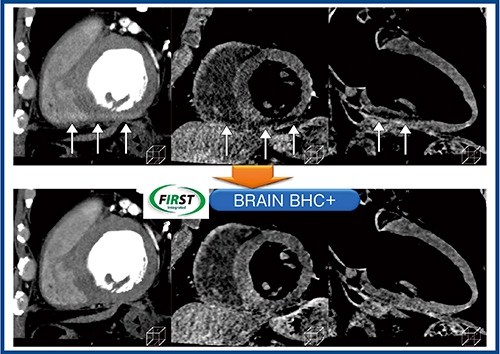

一方で,SMILIEの使用に当たっては,その限界を認識しておく必要がある。一つは,beam hardeningやcorn beam artifactの影響である。特に,下壁領域でアーチファクトが出やすいが,SMILIEではサブトラクションを行うためその影響が大きくなる。当施設の連続例では,64例中8例(12.5%)で評価困難な画像となった。この線状・帯状のアーチファクトを除去する方法として,MBIRである“FIRST”のモードを,“CARDIAC”ではなく“BRAIN”を適用し,強いBHCをかける方法が考えられる(図6)。もう一つは,十分なコントラストを得るための造影剤の使用量だが,冠動脈の造影剤だけではコントラストが不足するため,現状では400mgl/kg(冠動脈+大動脈)程度が必要と考えられる。

図6 Beam hardeningアーチファクトに対するFIRST(BRAIN)の適用